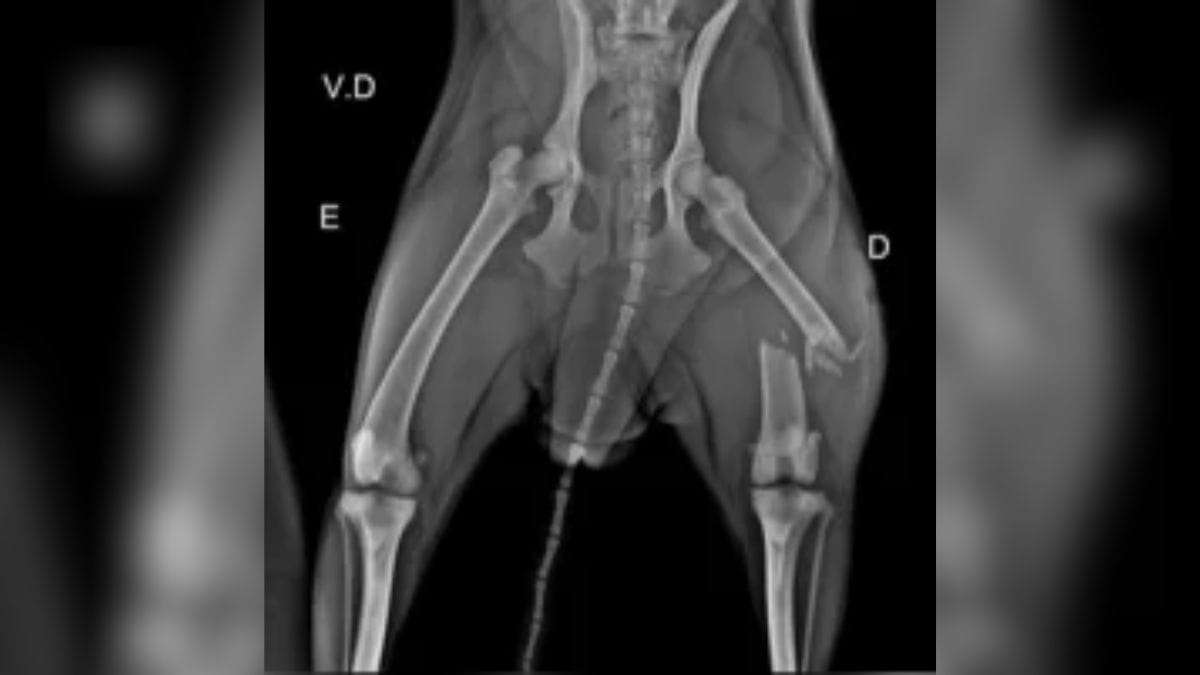

Desde que foi resgatada, Faísca ficou aos cuidados da Grupra, uma Organização não governamental (ONG) da cidade, e passou por diversos cuidados veterinários. A associação chegou a iniciar uma campanha online para custear os exames, procedimento cirúrgico no fêmur (que foi quebrado em diversas partes) e diárias na clínica.

A morte de Faísca foi confirmada pela ONG nas redes sociais. “Foi feito a cirurgia no fêmur, porém recebemos a informação que ela não resistiu. Nosso coração está em pedaços”, afirmou a Grupra.